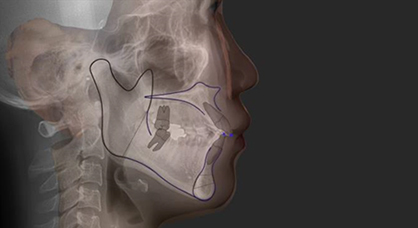

이차원 진단Surgical Treatment Objective(STO)

삼차원 영상과 방사선 사진을 중첩하여

수술 계획을 세웁니다.